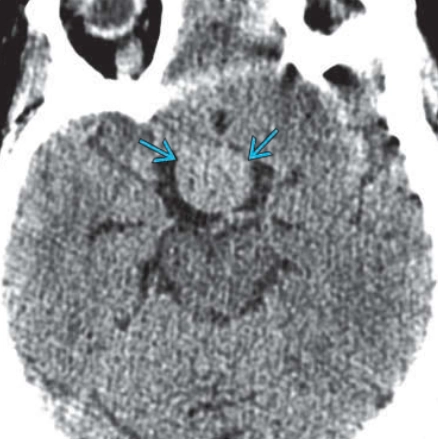

• Đột quỵ tuyến yên (Pituitary apoplexy)